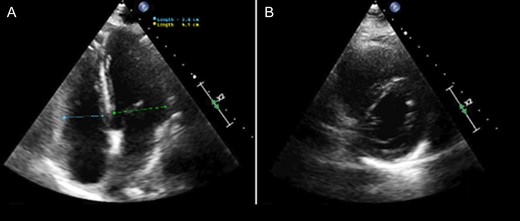

Post-operatively after 48 h, the patient was clinically improving with recovery of her RV function and off inotropic support. A bedside echocardiogram was performed showing an RV/LV ratio of 1.1. The patient was taken to the operating room (OR) for removal of liver packs, abdominal wall closure, decannulation of VA-ECMO, placement of IVC filter and surgical drains by the liver. The patient was hemodynamic stable post-operatively; off inotropic support and stable hematocrits. Despite physiologic improvements, she had altered mental status and left sided weakness. An MRI of the brain showed a subacute infarct of the right caudate lobe. Two days after her final operation, a repeat echocardiogram showed a normal RV functioning and RV/LV ratio of 0.7 (Fig. 5). On post-operative Day 4 the patient’s surgical drains were noted to have bloody output. Imaging showed a left hepatic artery pseudoaneurysm and underwent embolization.

Echocardiogram performed 2 days after removal of VA-ECMO cannulation showing a normalized RV/LV ratio without evidence of RV dysfunction. (A) Four-chamber apical view. (B) Parasternal short access view.